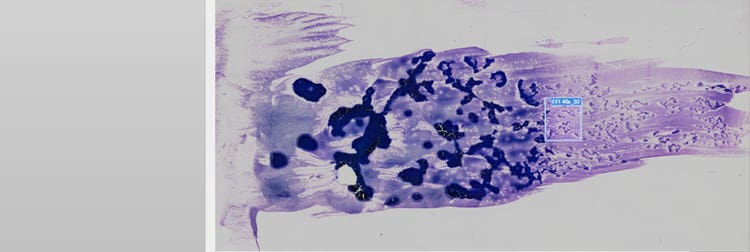

Imaging eines kompletten Objektträgers mit einer Probe aus dem peripheren Blut

Abbildung 1: Probe aus dem peripheren Blut eines Patienten mit akuter promyelozytärer Leukämie, gescannt mit dem Objektträger-Scannereinheit VS200 für die Forschung. Bilder mit freundlicher Genehmigung von Jana Kirsten, Institut für Klinische Chemie und Laboratoriumsmedizin am Universitätsklinikum Regensburg.

Bei dieser Anwendung zeigt das periphere Blut die neoplastischen Promyelozyten mit bilobierten Kernen oder extremen Granula (Abbildung 2, oranger Pfeil). Diese neoplastischen Promyelozyten finden sich auch im Knochenmark, ebenso wie myeloische Blastenzellen mit ganzen Bündeln von Auerstäbchen (grüner Pfeil in A, B und C). Auf diese sollte bei einem Verdacht auf APL geachtet werden.